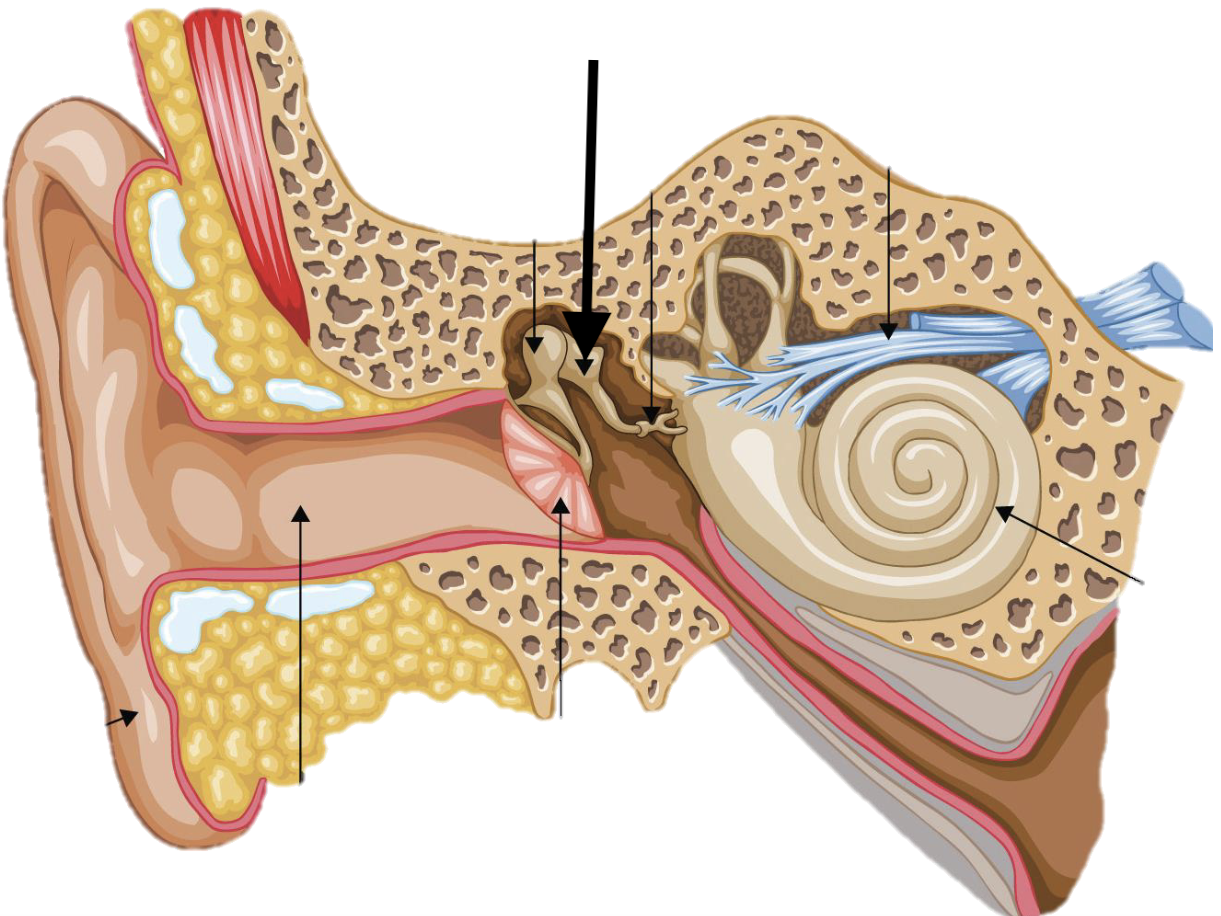

Name the feature of the ear ossicle

External acoustic meatus

Name the feature of the ear ossicle

Malleus

Name the feature of the ear ossicle

Incus

Name the feature of the ear ossicle

Stapes

Name the feature of the ear ossicle

Internal acoustic meatus

Name the feature of the ear ossicle

Cochlea

Name the feature of the ear ossicle

Temporal bone